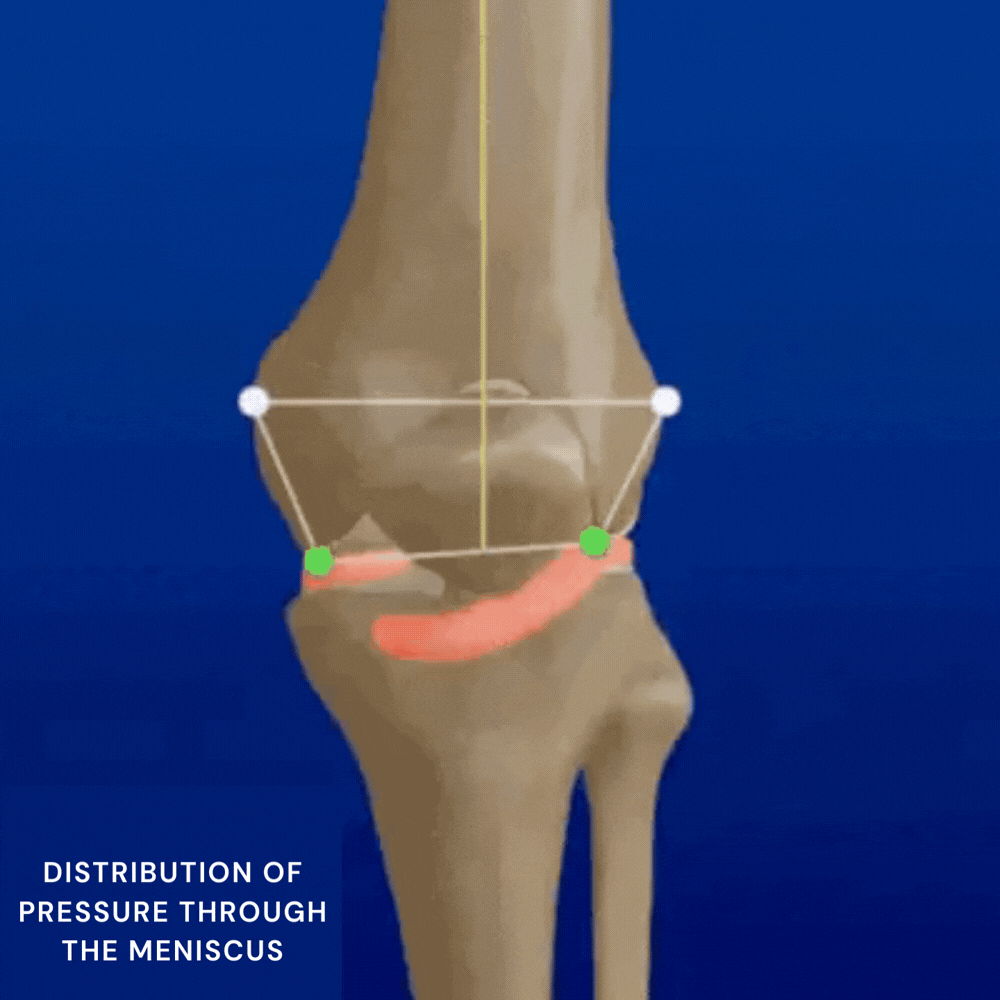

Instead of constricting or fixing the entire knee, BAT gently guides the kneecap back into its natural path of movement and distributes pressure evenly throughout the joint with every movement.

When pressure is redistributed, irritation subsides, movements feel easier, and the strain on the knee is significantly reduced. BAT doesn’t mask pain – it helps the knee move and function as intended.